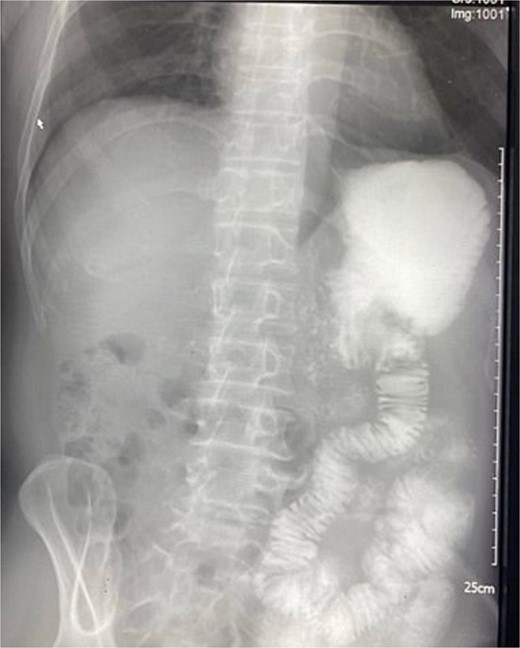

A 74-year-old man was admitted to the emergency department with severe, unremitting abdominal pain. Physical examination revealed guarding and rigidity. Plain abdominal X-rays revealed free gas under both hemi-diaphragms (Fig. 1). His medical history recorded arthritis, for which he has been treated with NSAID and corticosteroids for over 3 months. An indication of emergency laparotomy was performed for the patient with an initial diagnosis of generalized peritonitis due to gastrointestinal perforation.

X-ray showing free air under both hemi-diaphragms, indicative of gastrointestinal perforation.

Peptic ulcer perforation remains a prevalent surgical emergency with significant morbidity and mortality, particularly among elderly patients [6, 7]. Clinical symptoms and signs of peptic perforation can be various amongst patients, but this case illustrated typical symptoms with sudden onset of abdominal pain with guarding and rigidity. The X-ray image of free air under both hemi-diaphragm reenforced the diagnosis.